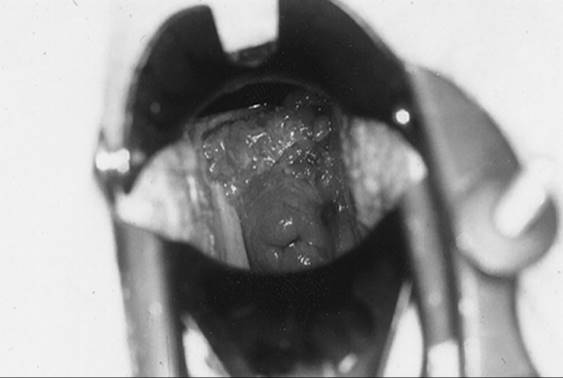

Patients with VIN most commonly present with pruritis and vulvar lesions. These lesions may appear scaly, white, red, or hyperpigmented (Fig. 51.1, Fig. 51.2, Fig. 51.3 and Fig. 51.4). Careful inspection with 5% acetic acid and liberal use of punch biopsy are the cornerstones of diagnosis. An underlying malignancy may be present in 7% to 22% of patients who undergo surgical excision for vulvar carcinoma in situ. Wide local excision with at least a 5-mm margin is the preferred management option as it allows pathologic confirmation and is associated with less morbidity than skinning vulvectomy. Skinning vulvectomy with split thickness skin graft may be an option in patients with widespread disease. Laser ablation is also an effective nonmutilating option in patients with multifocal or clitoral disease. Recurrences are frequent (10%–50%) despite negative surgical margins and therapy should be tailored to symptom control and ruling out underlying malignancy. Patients should be followed every few months with careful visual inspection of the vulva and taught self-exam skills as well.

FIG. 51.2. Vulvar carcinoma in situ before application of 5% acetic acid. See color figure 51.2.

FIG. 51.3. Vulvar carcinoma in situ after application of 5% acetic acid. See color figure 51.3.